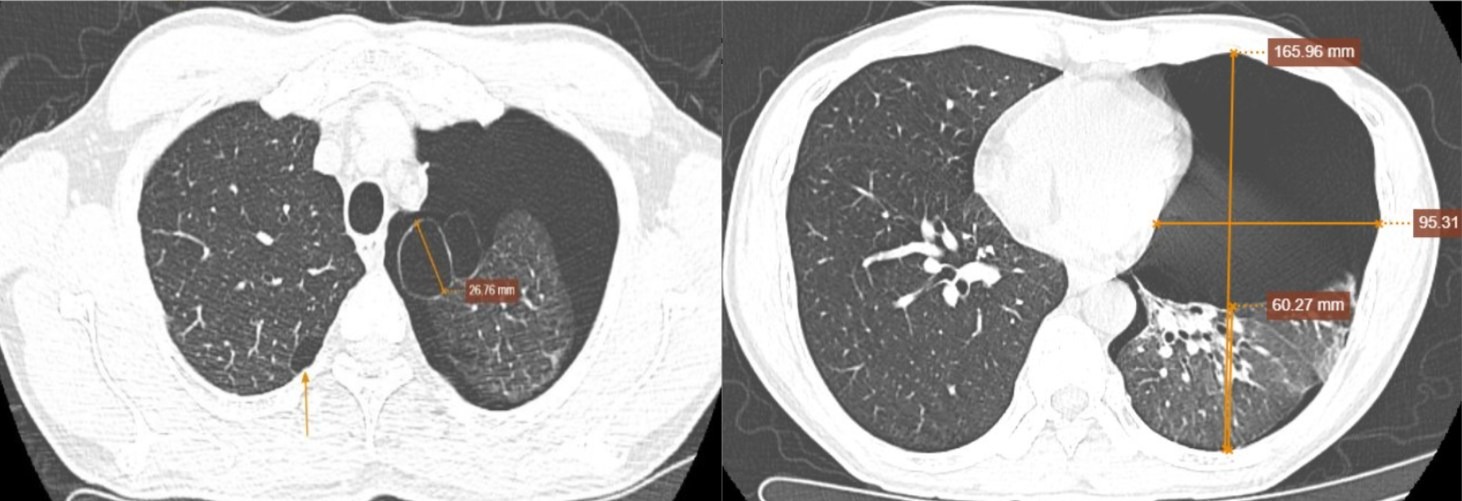

Phim chụp của bệnh nhân.

Nhịp tim đều 98 lần/phút, huyết áp 140/90 mmHg, SpO₂ 95%. Kết quả CT liều thấp ghi nhận tràn khí khoang màng phổi trái mức độ nhiều, khiến phổi xẹp thụ động tới 75%, nghĩ nhiều đến nguyên nhân vỡ kén khí.

Hình ảnh còn cho thấy kén khí thùy trên phổi trái và giãn phế nang cạnh vách hai phổi. Siêu âm tim, màng phổi cho thấy tim bị đẩy lệch sang phải, mất dấu trượt màng phổi và không còn đường B-line.